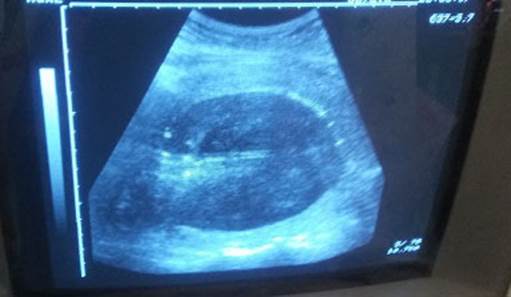

Se extrajo recién nacido femenino con test de Apgar 8/9 y peso de 4025 g. Se realizó alumbramiento activo y se constató hemorragia obstétrica mayor por atonía uterina (pérdida aproximada del 25 % de la volemia), refractaria al tratamiento médico y se decidió realizar manejo conservador del útero, mediante el taponamiento endouterino con balón de Bakri. En el propio salón de partos se realizó reposición volumétrica con cristaloides y protocolos de transfusión masiva (glóbulos, plasma y plaquetas) en correspondencia con el grado de shock diagnosticado (leve). Se comprobó mediante ecografía abdominal la colocación adecuada del balón y se logró contractilidad uterina y hemostasia. (Figuras 1 y 2). Finalizó el procedimiento sin otras complicaciones y luego de alcanzar la estabilidad hemodinámica de la paciente, esta fue trasladada a Unidad de Cuidados Intensivos Polivalentes, para mejor seguimiento de su condición.